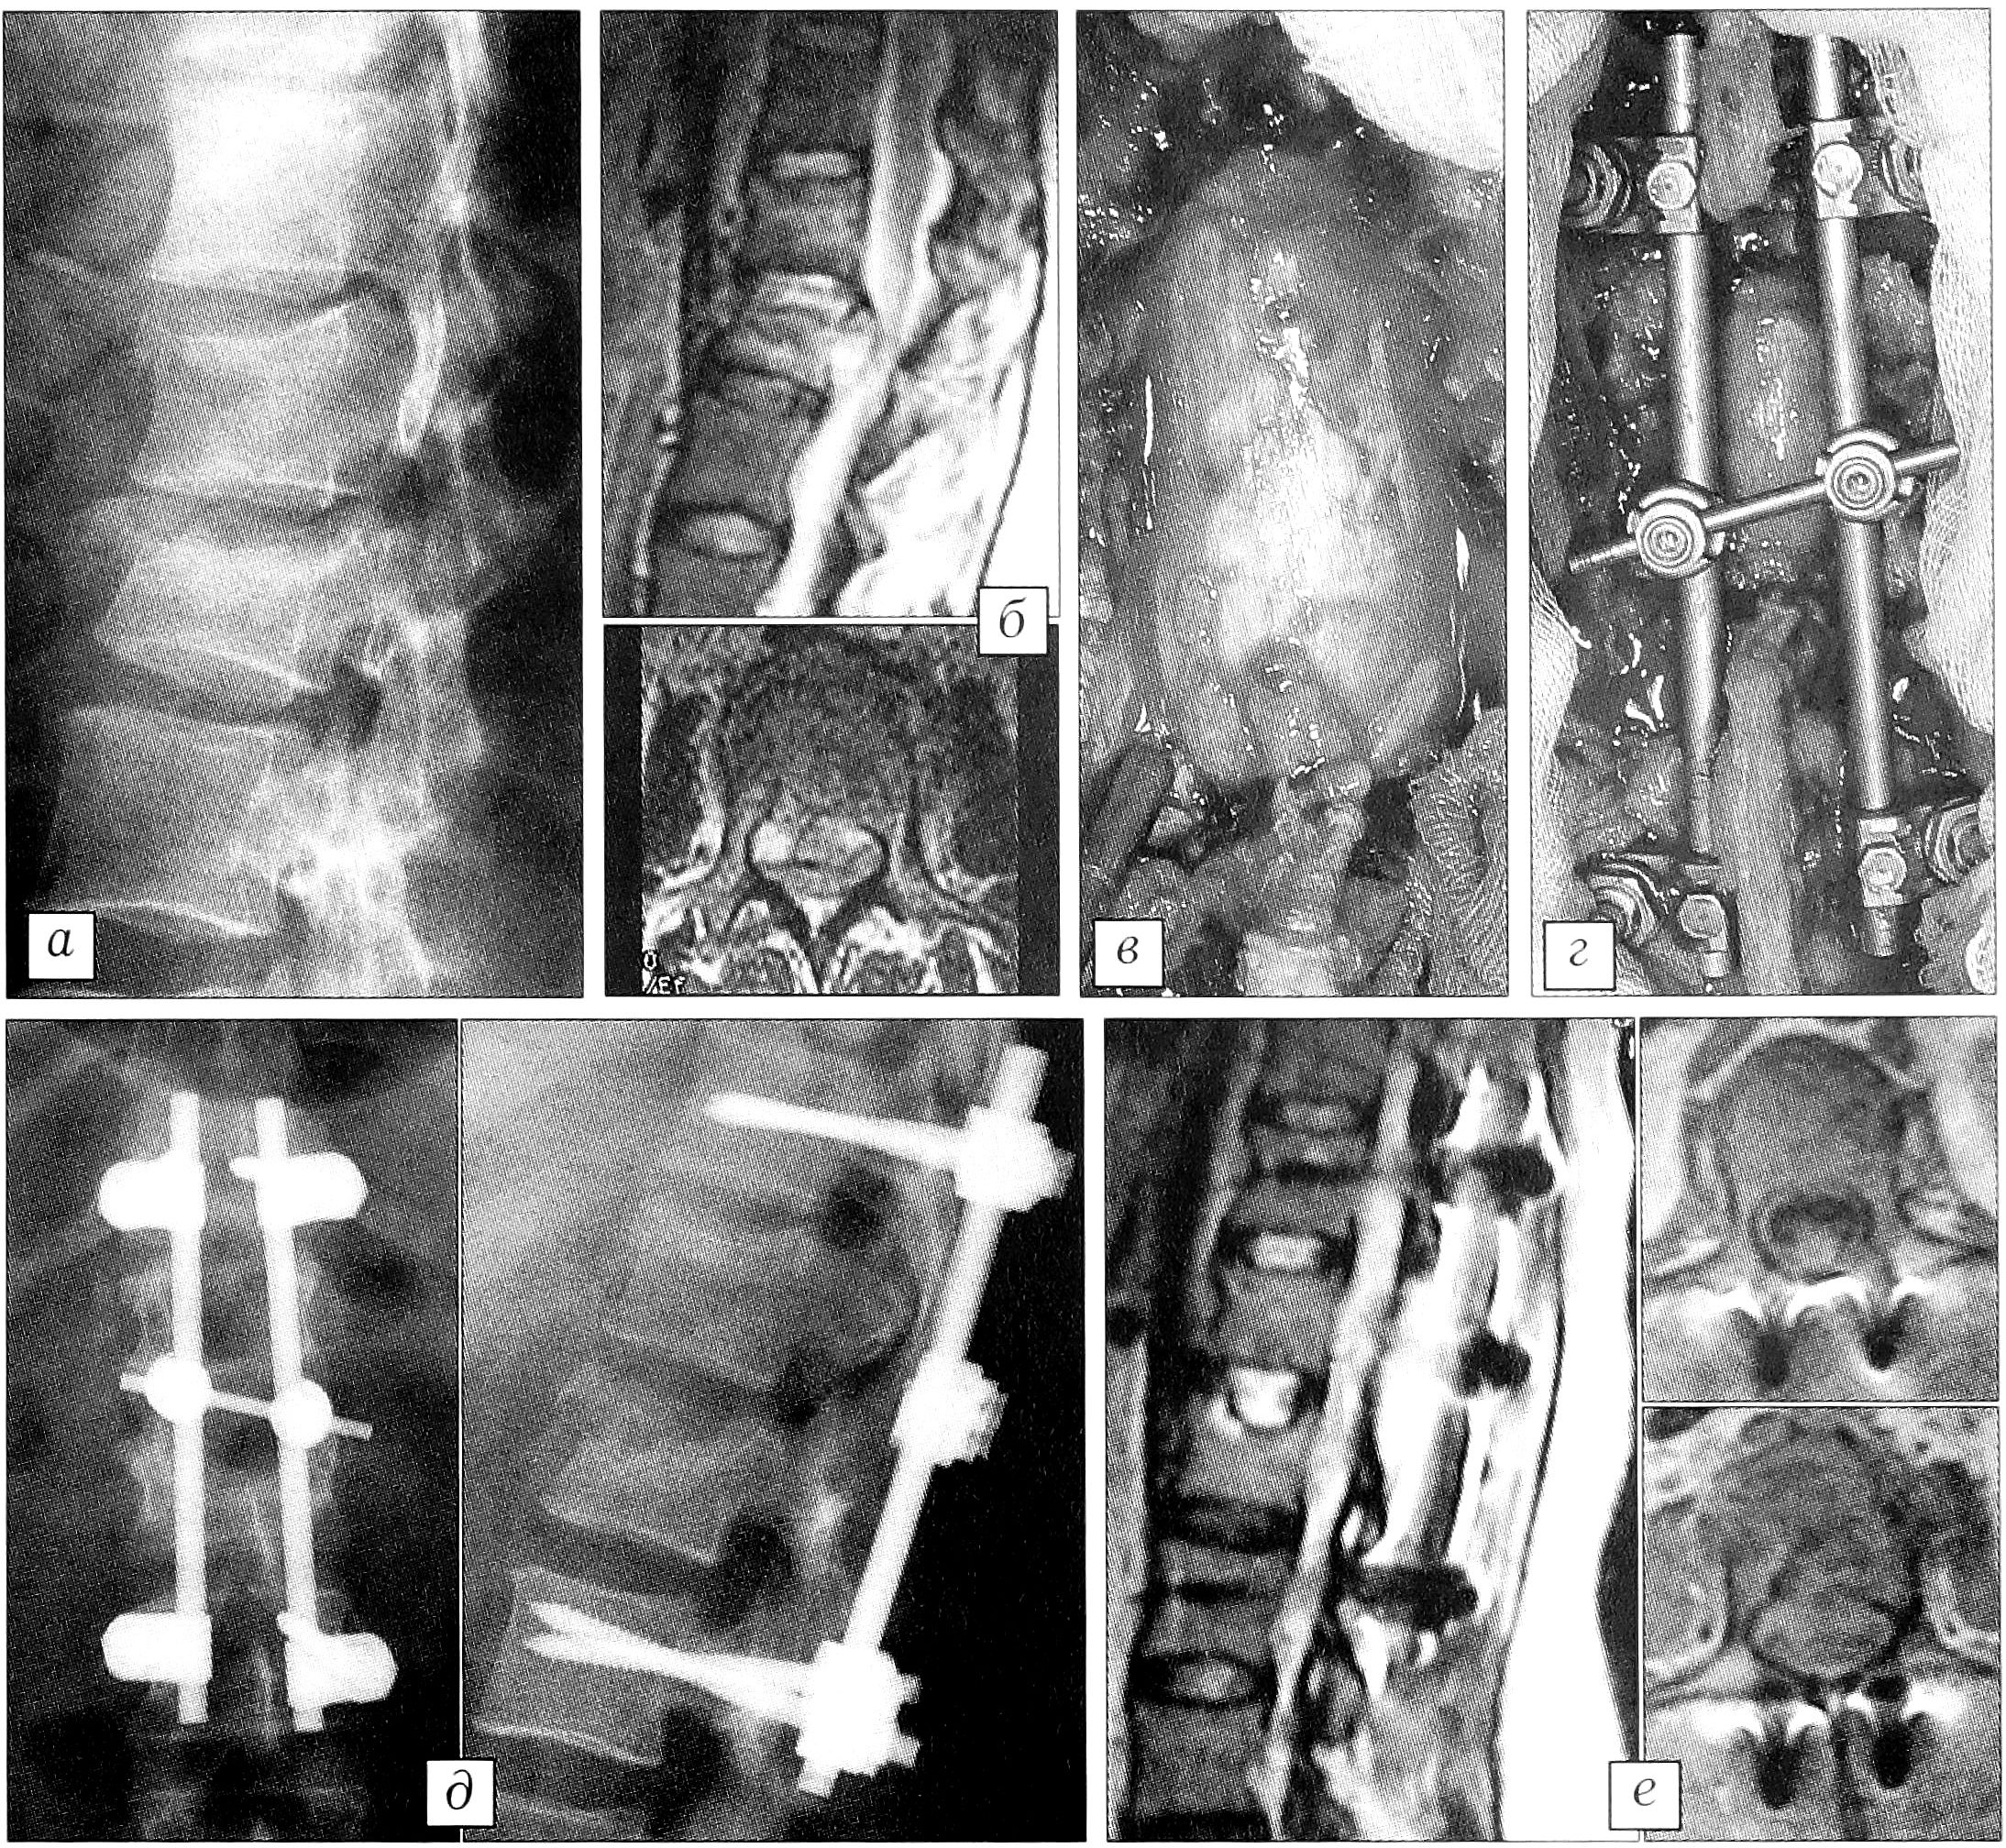

На рис. 2 представлен результат лечения осложненного перелома первого и второго поясничных позвонков у 37-летней пациентки. Клиническая картина включала нижнюю параплегию и нарушение функции тазовых органов. Через 16 ч после травмы больной произведены декомпрессивная ламинэктомия, менингомиелорадикулолиз, репозиция, восстановление высоты позвонка путем пластики тела аутокостной крошкой через ножку позвонка и фиксация системой USS. Через 6 нед — полное восстановление, пациентка вернулась к привычной работе.

Рис.2. Больная 3. 37 лет. а — рентгенограмма при поступлении: компрессионный осложненный перелом L1—2; б — МРТ при поступлении: компрессия корешков конского хвоста телом L2; в — декомпрессия дурального мешка; г — фиксация USS; д — рентгенограммы после операции; е — МРТ после операции: полноценная реконструкция позвоночного канала.